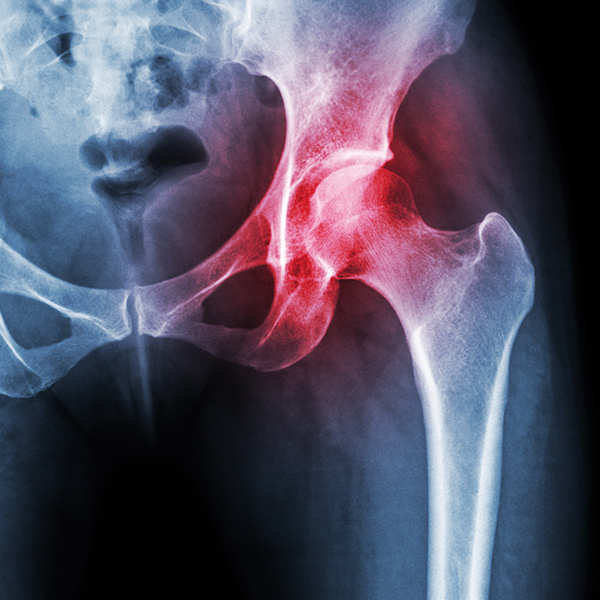

股関節(こかんせつ)は、蝶々のような形の骨盤(こつばん)と大腿骨(だいたいこつ)という太ももの骨とで構成されています。大腿骨の付け根には、球の形をした大腿骨頭(だいたい こっとう)があります。骨盤にはその受け皿のような形の臼蓋(きゅうがい)があり、ソケットがはまるようになってるので、股関節を動かすことができます。

股関節には、他の関節と同じように軟骨があり、関節の動きを滑らかにしています。しかし、軟骨がすり減ったり、骨頭が変形したり、受け皿側の臼蓋がすり減るなどして、骨が変形してしまうことがあります。こうした症状が起きると、長時間立っていたり、歩いたりすると、足の付け根が痛くなったり、足を動かせる範囲が狭くなったりします。